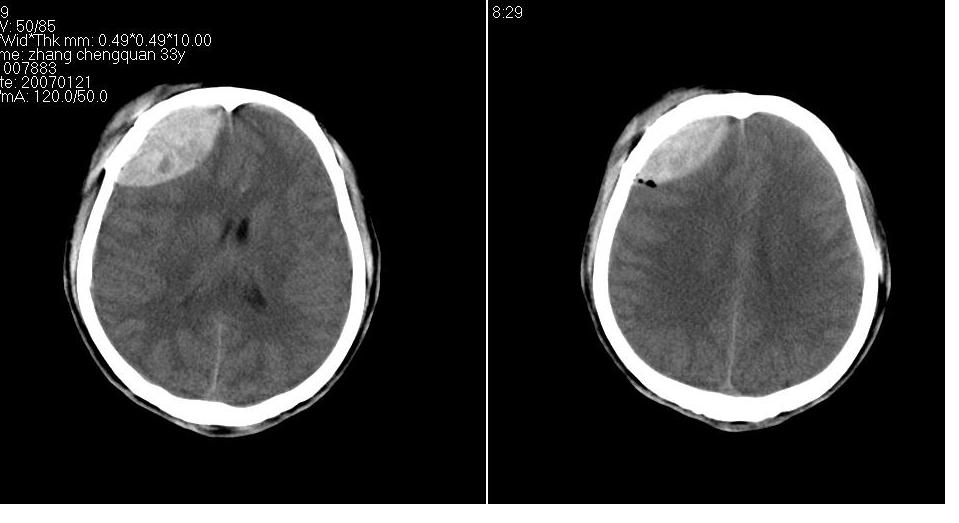

以下是引用卜一在2007-1-25 16:08:00的发言:[br]1 眼眶外侧壁 内侧壁 右侧筛窦 额骨鳞部_粉碎型骨折,并骨片植入眼眶内.[br]2 右侧额区硬膜外血肿伴积气.[br]3 眼眶内积气 筛窦内积血.

以下是引用卜一在2007-1-25 16:08:00的发言:[br]1 眼眶外侧壁 内侧壁 右侧筛窦 额骨鳞部_粉碎型骨折,并骨片植入眼眶内.[br]2 右侧额叶硬膜外血肿伴积气.[br]3 眼眶内积气 筛窦内积血.